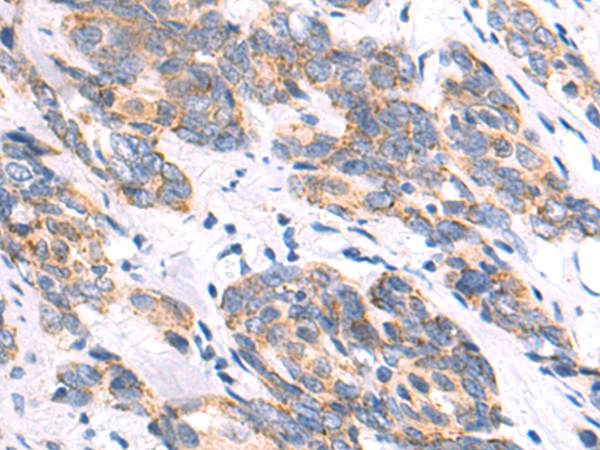

分类: 科研抗体货号: P04873别名: C4orf7; FDC-SP应用: IHC反应种属: Human